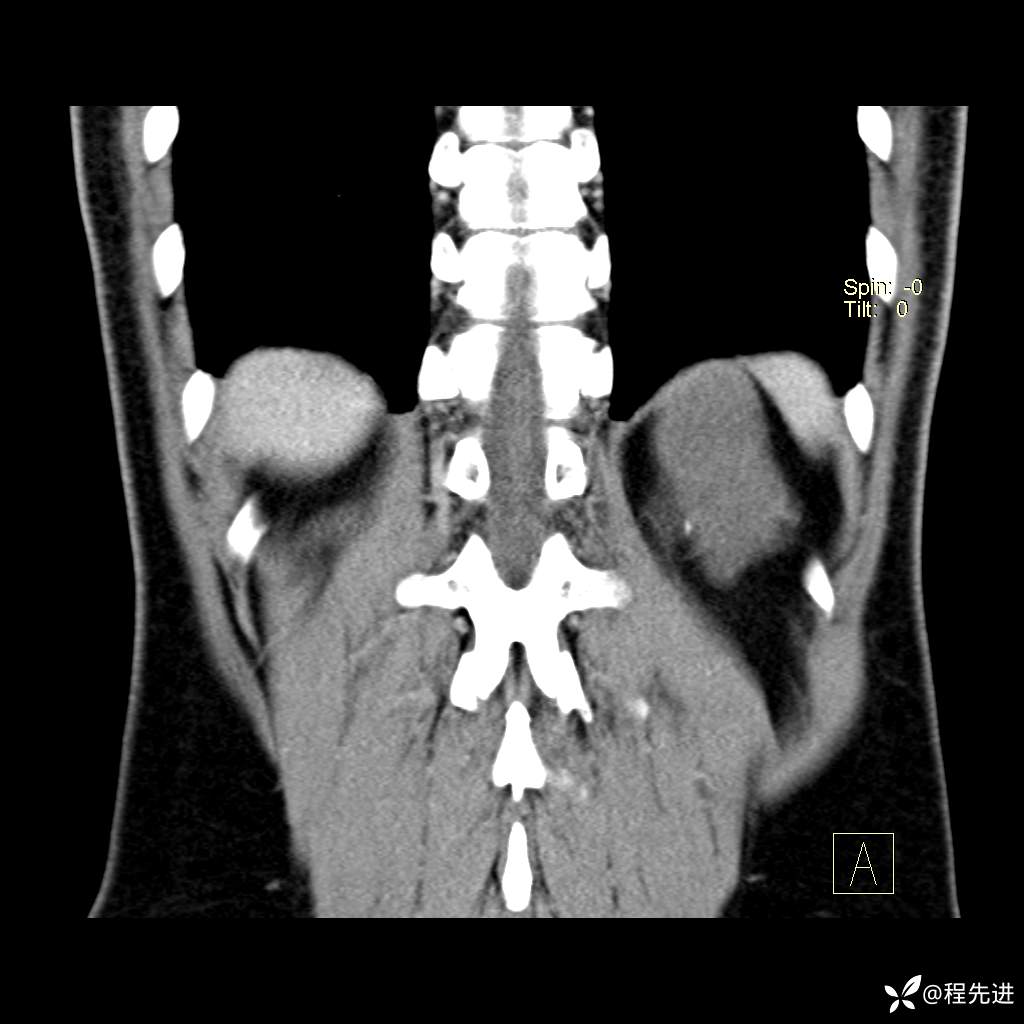

CT平扫:(CT值:平扫,27HU,动脉期,27HU,门静脉期,31HU,平衡期,32HU)

冠状位重建: